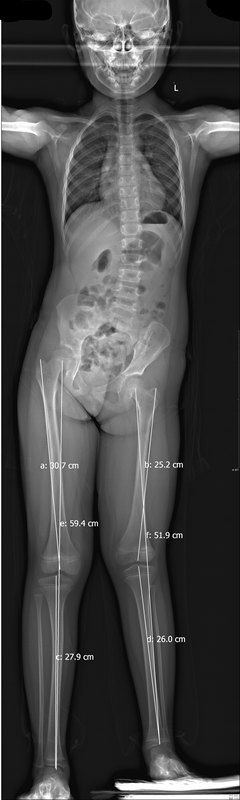

儿童双下肢不等长(一)诊断与评估

双下肢不等长是儿童生长发育时期的常见现象,有些从一出生就出现,有些到青春期出现脊柱侧弯才发现是双下肢不等长所导致。“长短脚”的危害很大,持续双下肢不等长会导致患儿行走步态异常,步态起伏会造成行走时能量消耗增加、容易疲劳,较短肢体容易出现跟腱挛缩,持续骨盆倾斜继发较长一侧的髋关节不稳定,久而久之出现髋关节发育不良,脊柱代偿性侧弯,晚期出现腰痛及髋关节退行性关节炎等一系列问题。因此双下肢不等长应当是小儿骨科医生重点关注的问题。在治疗双下肢不等长之前,我们应当重点关注几个问题:1.双下肢不等长的病因有哪些?弄清病因有助于我们选择治疗方式,创伤、感染、肿瘤、先天畸形都有可能造成下肢不等长,有些患儿有明确的创伤、感染病史,家族遗传疾病史,有些需要影像学检查发现骨质异常明确诊断,也有患者通过各项检查均无法判断是何种异常,只是单纯的双下肢长度和周径不一(表1)。表1:双下肢不等长病因患侧过度生长患侧短缩DDH术后过度生长腓侧轴旁半肢骨折后过度生长内生软骨瘤病神经纤维瘤病骺早闭血管瘤股骨头坏死单侧肢体肥大Perthes病巨肢股骨头骺滑脱纤维异样增殖症半肢发育不良2.如何评估双下肢不等程度?站立位双下肢全长测量片可以帮我们精确测量双下肢不等长的具体数值(图1)。要注意的是:不能仅仅关注股骨头最高点到踝关节中心的距离,对于DDH术后的患者,可能也存在双髂骨的不等长;对于腓侧轴旁半肢或巨肢的患者,也可能存在足的高度不一。另外,有条件的话,应当在穿鞋补高前和补高后对比拍摄脊柱平片,判断姿势性脊柱侧弯是否能够通过补高鞋获得矫正。3.家长还应该注意些什么?明确肢体不等长的病因、精准测量长度差之后,家长还应该密切关注长度差随生长发育的变化,长度差是否恒定,还是随着生长发育逐年增加。如果有连续几年的长度评估,再综合分析骨龄情况,可以大致预测生长发育成熟时最终的长度差,有助于医生制定长远的治疗计划。